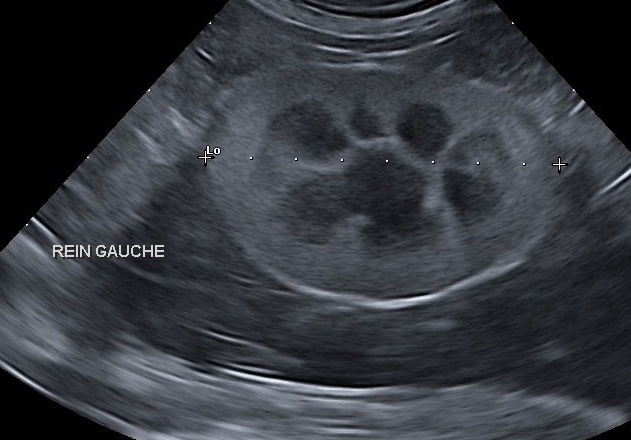

abdominale

L'échographie permet d'explorer les différents organes de l'abdomen (tissus mous) : foie, rate, reins, vessie...elle est utile pour diagnostiquer et suivre certaines pathologies. Elle permet également d'assurer le suivi de gestation.

Cytoponctions et biopsies échoguidées

Sous contrôle échographique, nous réalisons des prélèvements à visée diagnostique (ponctions à l'aiguille fine, biopsies) et le recueil d'urine de façon stérile.